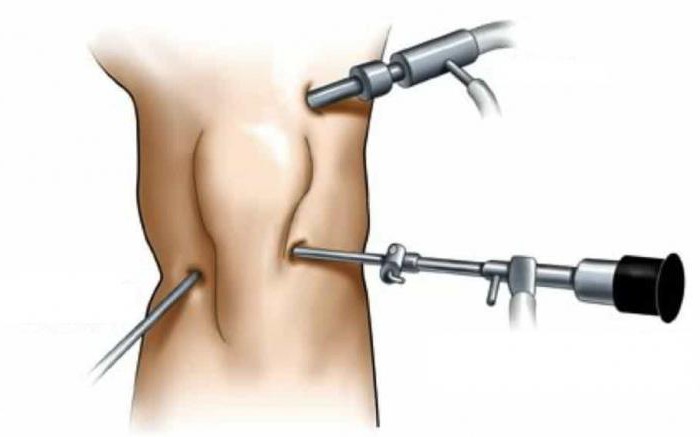

The cost of knee arthroplasty is currently quite high - from 50,000 rubles only for the intervention itself, and, in addition, you will have to pay for hospital stay, used drugs, all the studies that will be carried out, as well as the prosthesis. Many believe that the intervention is worth the money, because we are talking about an operation in which the damaged parts of the knee are successfully restored, the person gets the opportunity to move normally. The issue is extremely topical, many of our compatriots suffer from knee problems. For others, the cause is trauma; in others, age-related changes that destroy joint tissue.